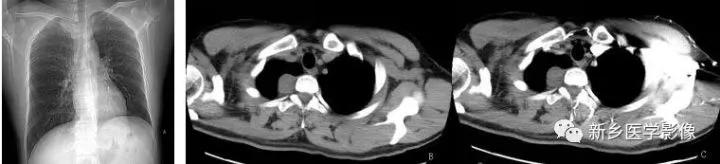

右上纵隔神经鞘瘤CT图像

a. 胸部正位片示右上纵隔脊柱旁圆形软组织密度影。b. CT平扫示右侧后上纵隔脊柱旁圆形软组织密度肿块影,密度均匀,边缘光整。c. CT增强示病灶轻度强化,密度均匀。d. CT增强矢状位重组图示肿块位于后上纵隔,与脊椎关系密切。